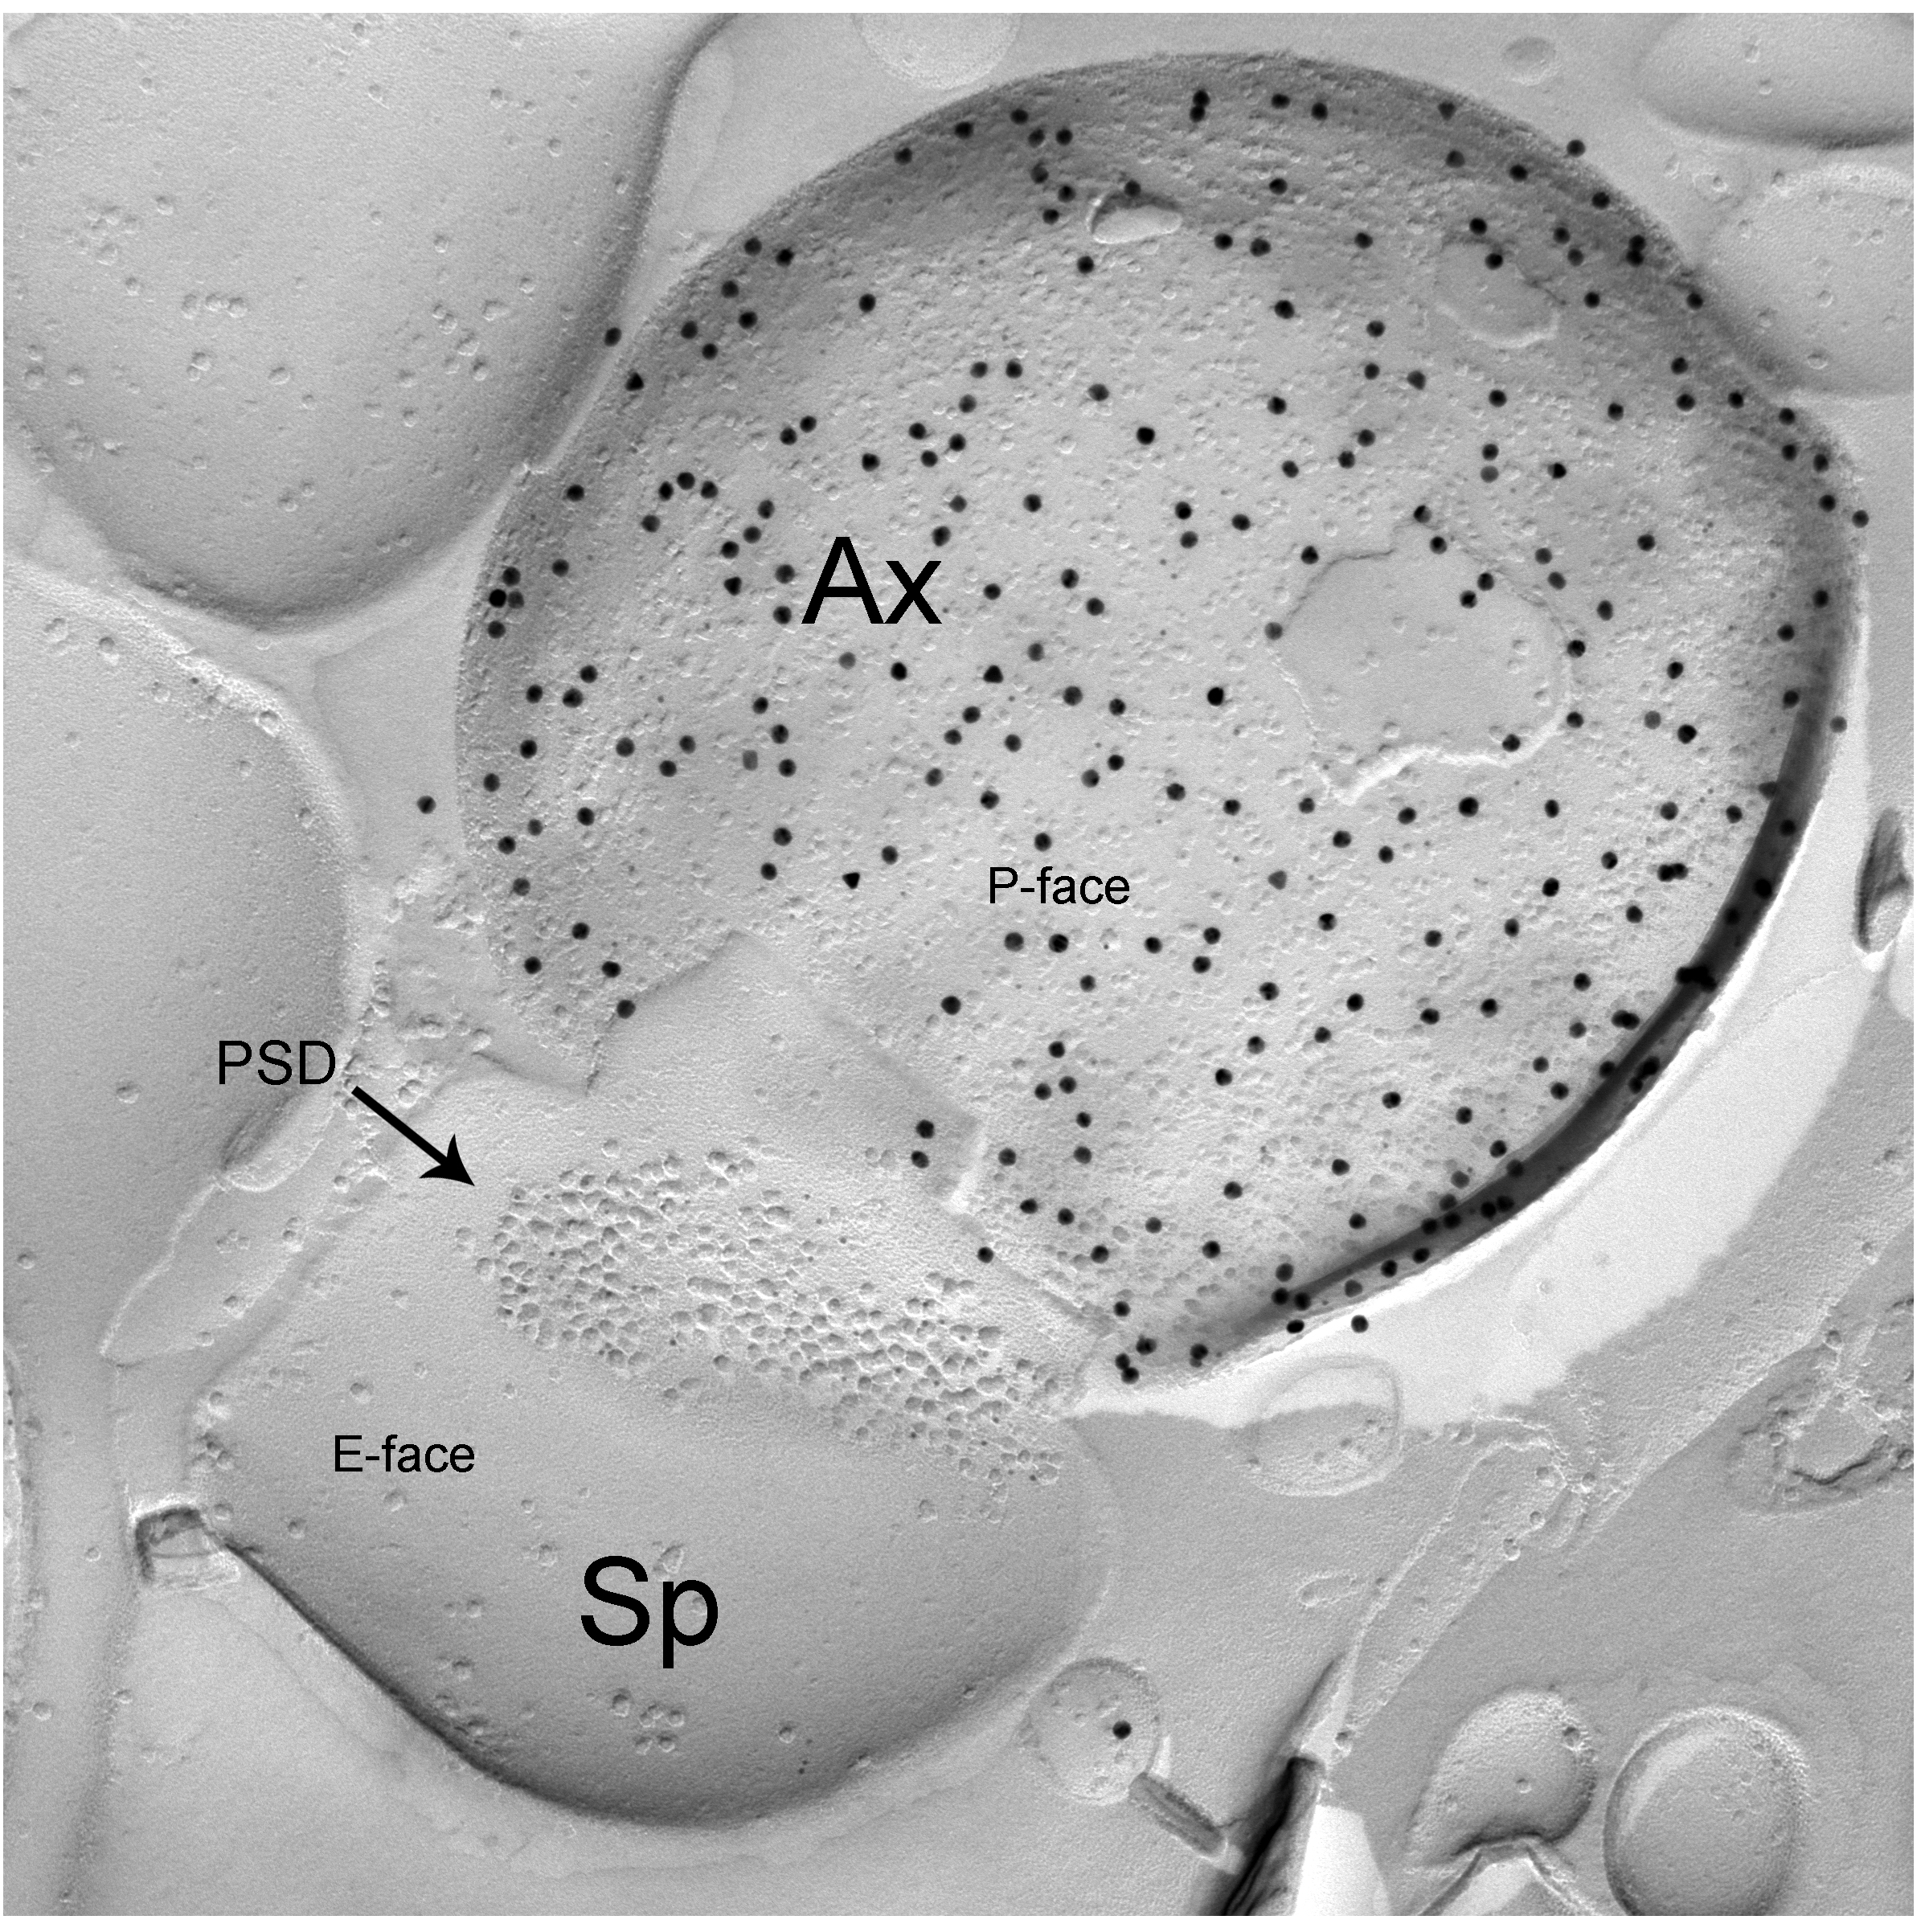

Taking advantage of recent developments in molecular genetics, viral trans-synaptic tracing and novel ultrastructural techniques (e.g. freeze-fracture replica immunogold labelling or FRIL), we investigate long-range connections between amygdala GABAergic neurons (e.g. interneurons of the BLA or ITC) and cortical or subcortical brain structures.

Kaufmann, W. A., Matsui, K., Jeromin, A., Nerbonne, J. M., & Ferraguti, F. (2013). Kv4.2 potassium channels segregate to extrasynaptic domains and influence intrasynaptic NMDA receptor NR2B subunit expression. Brain Struct Funct, 218(5), 1115-1132.